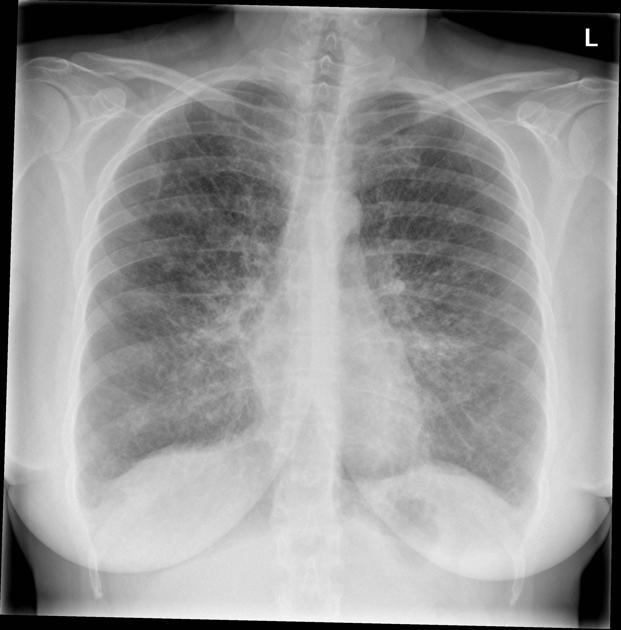

CLINICAL HISTORY:

46Yo Female

Left sided chest pain

FINDINGS:

Innumerable tiny nodules demonstrated bilaterally and evenly throughout the lungs. High density suggests calcification.

No acute pulmonary pathology is demonstrated. No pleural abnormalities demonstrated.

Heart size is normal. Hila and mediastinal contours are normal.

Skeletal review is unremarkable.

IMPRESSION:

Appearances are consistent with previous varicella pneumonia.

No cause for patient’s symptoms identified.

BACKGROUND:

Varicella pneumonia is a viral lung infection caused by the chickenpox virus (varicella-zoster). Initial infection will present with multiple nodules, these may resolve but in some cases (as here) calcify. Most cases of pneumonia are in immunocompromised adults.

DIFFERENTIAL DIAGNOSIS:

Correlation with previous post-infection imaging should show unchanged appearances.

DDX of dense miliary opacities: